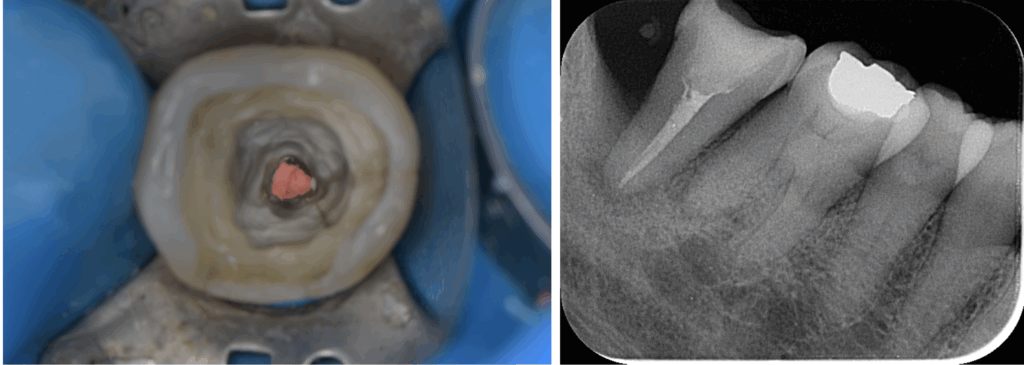

- マイクロスコープ:肉眼の最大25倍の拡大視野で根管の奥まで確認

さらにラバーダム防湿(治療歯だけを隔離するゴムシート)を使用し、治療中の再感染を徹底的に防ぎます。

- 感染源の除去(マイクロスコープ下で徹底清掃)

- 根管洗浄・消毒(薬液+超音波で隅々まで)

- 根管封鎖(隙間なく充填材で密閉)